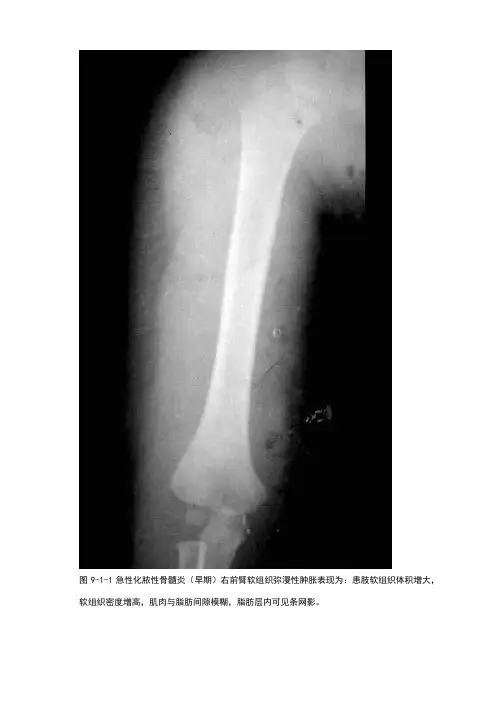

图9-1-1急性化脓性骨髓炎(早期)右前臂软组织弥漫性肿胀表现为:患肢软组织体积增大,软组织密度增高,肌肉与脂肪间隙模糊,脂肪层内可见条网影。